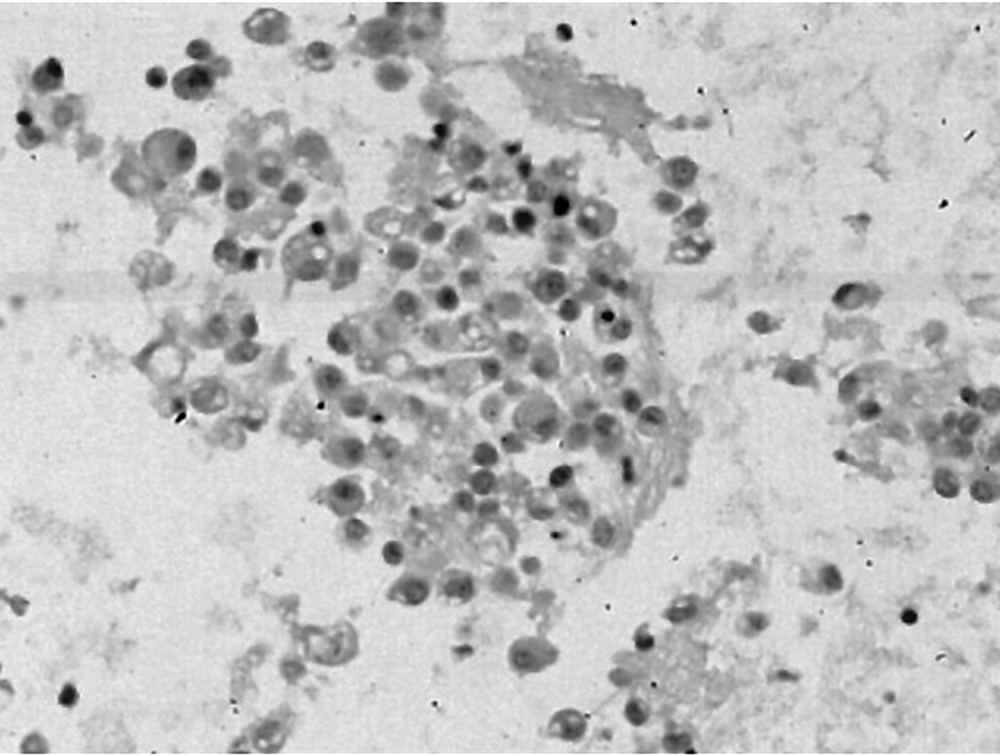

晚期胃癌目前无明确有效治疗手段,现报道1例安罗替尼治疗晚期胃癌病例,并对其临床疗效和安全性进行分析。